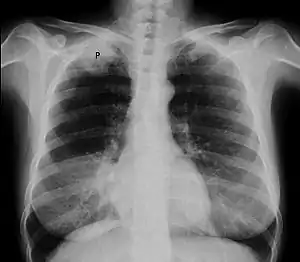

| Chest X-ray showing a Pancoast tumor (labeled as P, non-small cell lung carcinoma, right lung), from a 47-year-old female smoker. | |